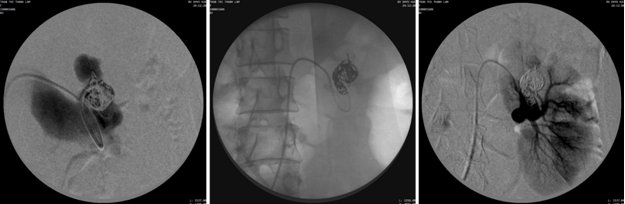

Hình 3. Thả coil lấp đầy túi phình lớn nhất để chặn đường ra, sau đó lấp dần luồn thông bằng các coil nhỏ hơn. Chụp kiểm tra thấy tắc hoàn toàn luồn thông, bảo tổn tưới máu cho nhu mô thận bình thường.